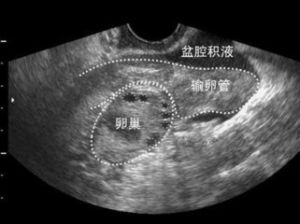

4、超聲檢查方便快捷,在盆腔積液檢查中對疾病的明確診斷方面有著明顯的優越性。相對於其他檢查診斷方法,超聲作為一種無創、無痛、方便的檢查手段,對各種原因引起的盆腔積液,可以根據超聲檢查,同時結合臨床資料及實驗室檢查,在明確診斷方面有著明顯的優越性。

5、彩超檢查,確定有無盆腔積液,進行彩超檢查是的檢查方法。可快速準確確定積液的量。

盆腔積液的位置多發生在子宮直腸陷窩等盆腔內位置較低處,婦科常用的有效檢查手段是B超,可以較準確的判斷積液的量。